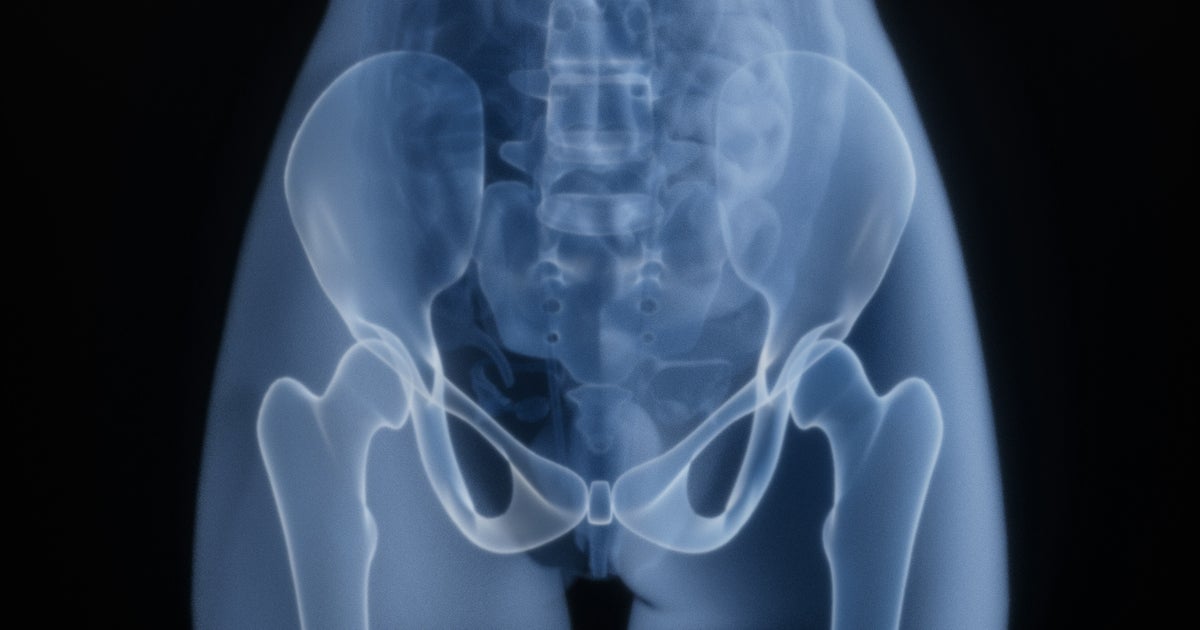

• A study involving 235 postmenopausal women found that consuming 50g (five to six) prunes daily for 12 months helped preserve bone density and strength at the hip, a critical weight-bearing area prone to fractures.

• Women who did not consume prunes experienced a 1.1% bone loss over the same period, while those who ate prunes maintained their bone density, suggesting potential for reducing fracture risk.